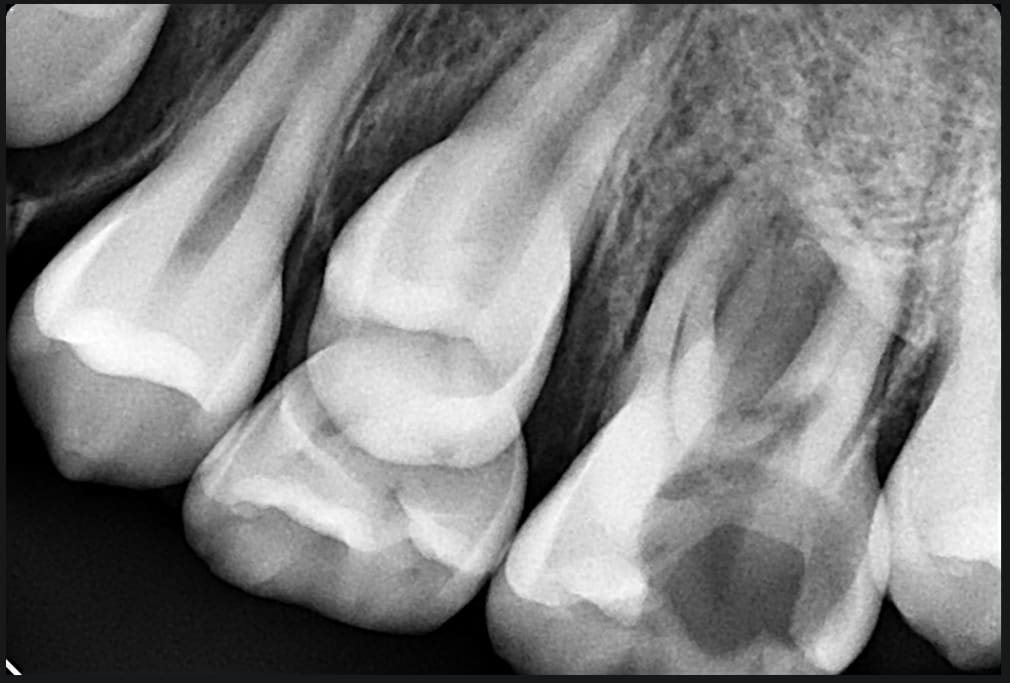

Mon coup de gueule de ce soir !!!

Je vous laisse voir la rétro.

Patiente de 11ans, C2S pas vu depuis 3ans avec ATCD de MIH, mais suivi depuis +2ans chez ODF.

A croire la mère un Quadhélix a été déposé y'a un peu plus de 6mois.

La 2ème que je récupère dans cet état là depuis de début de l'année.